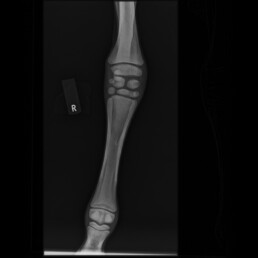

In der röntgenologischen Untersuchung der Tarsi und Carpi wurde eine hypoplastische Ossification Grad 2-3 festgestellt (schwach entwickelte Verknöcherung).

Abb. 2 – 0° rechte Vordergliedmaße: inkomplette Ossifikation der Carpalknochen Grad 2-3

Abb. 3 – 0° linke Vordergliedmaße: inkomplette Ossifikation der Carpalknochen Grad 2-3